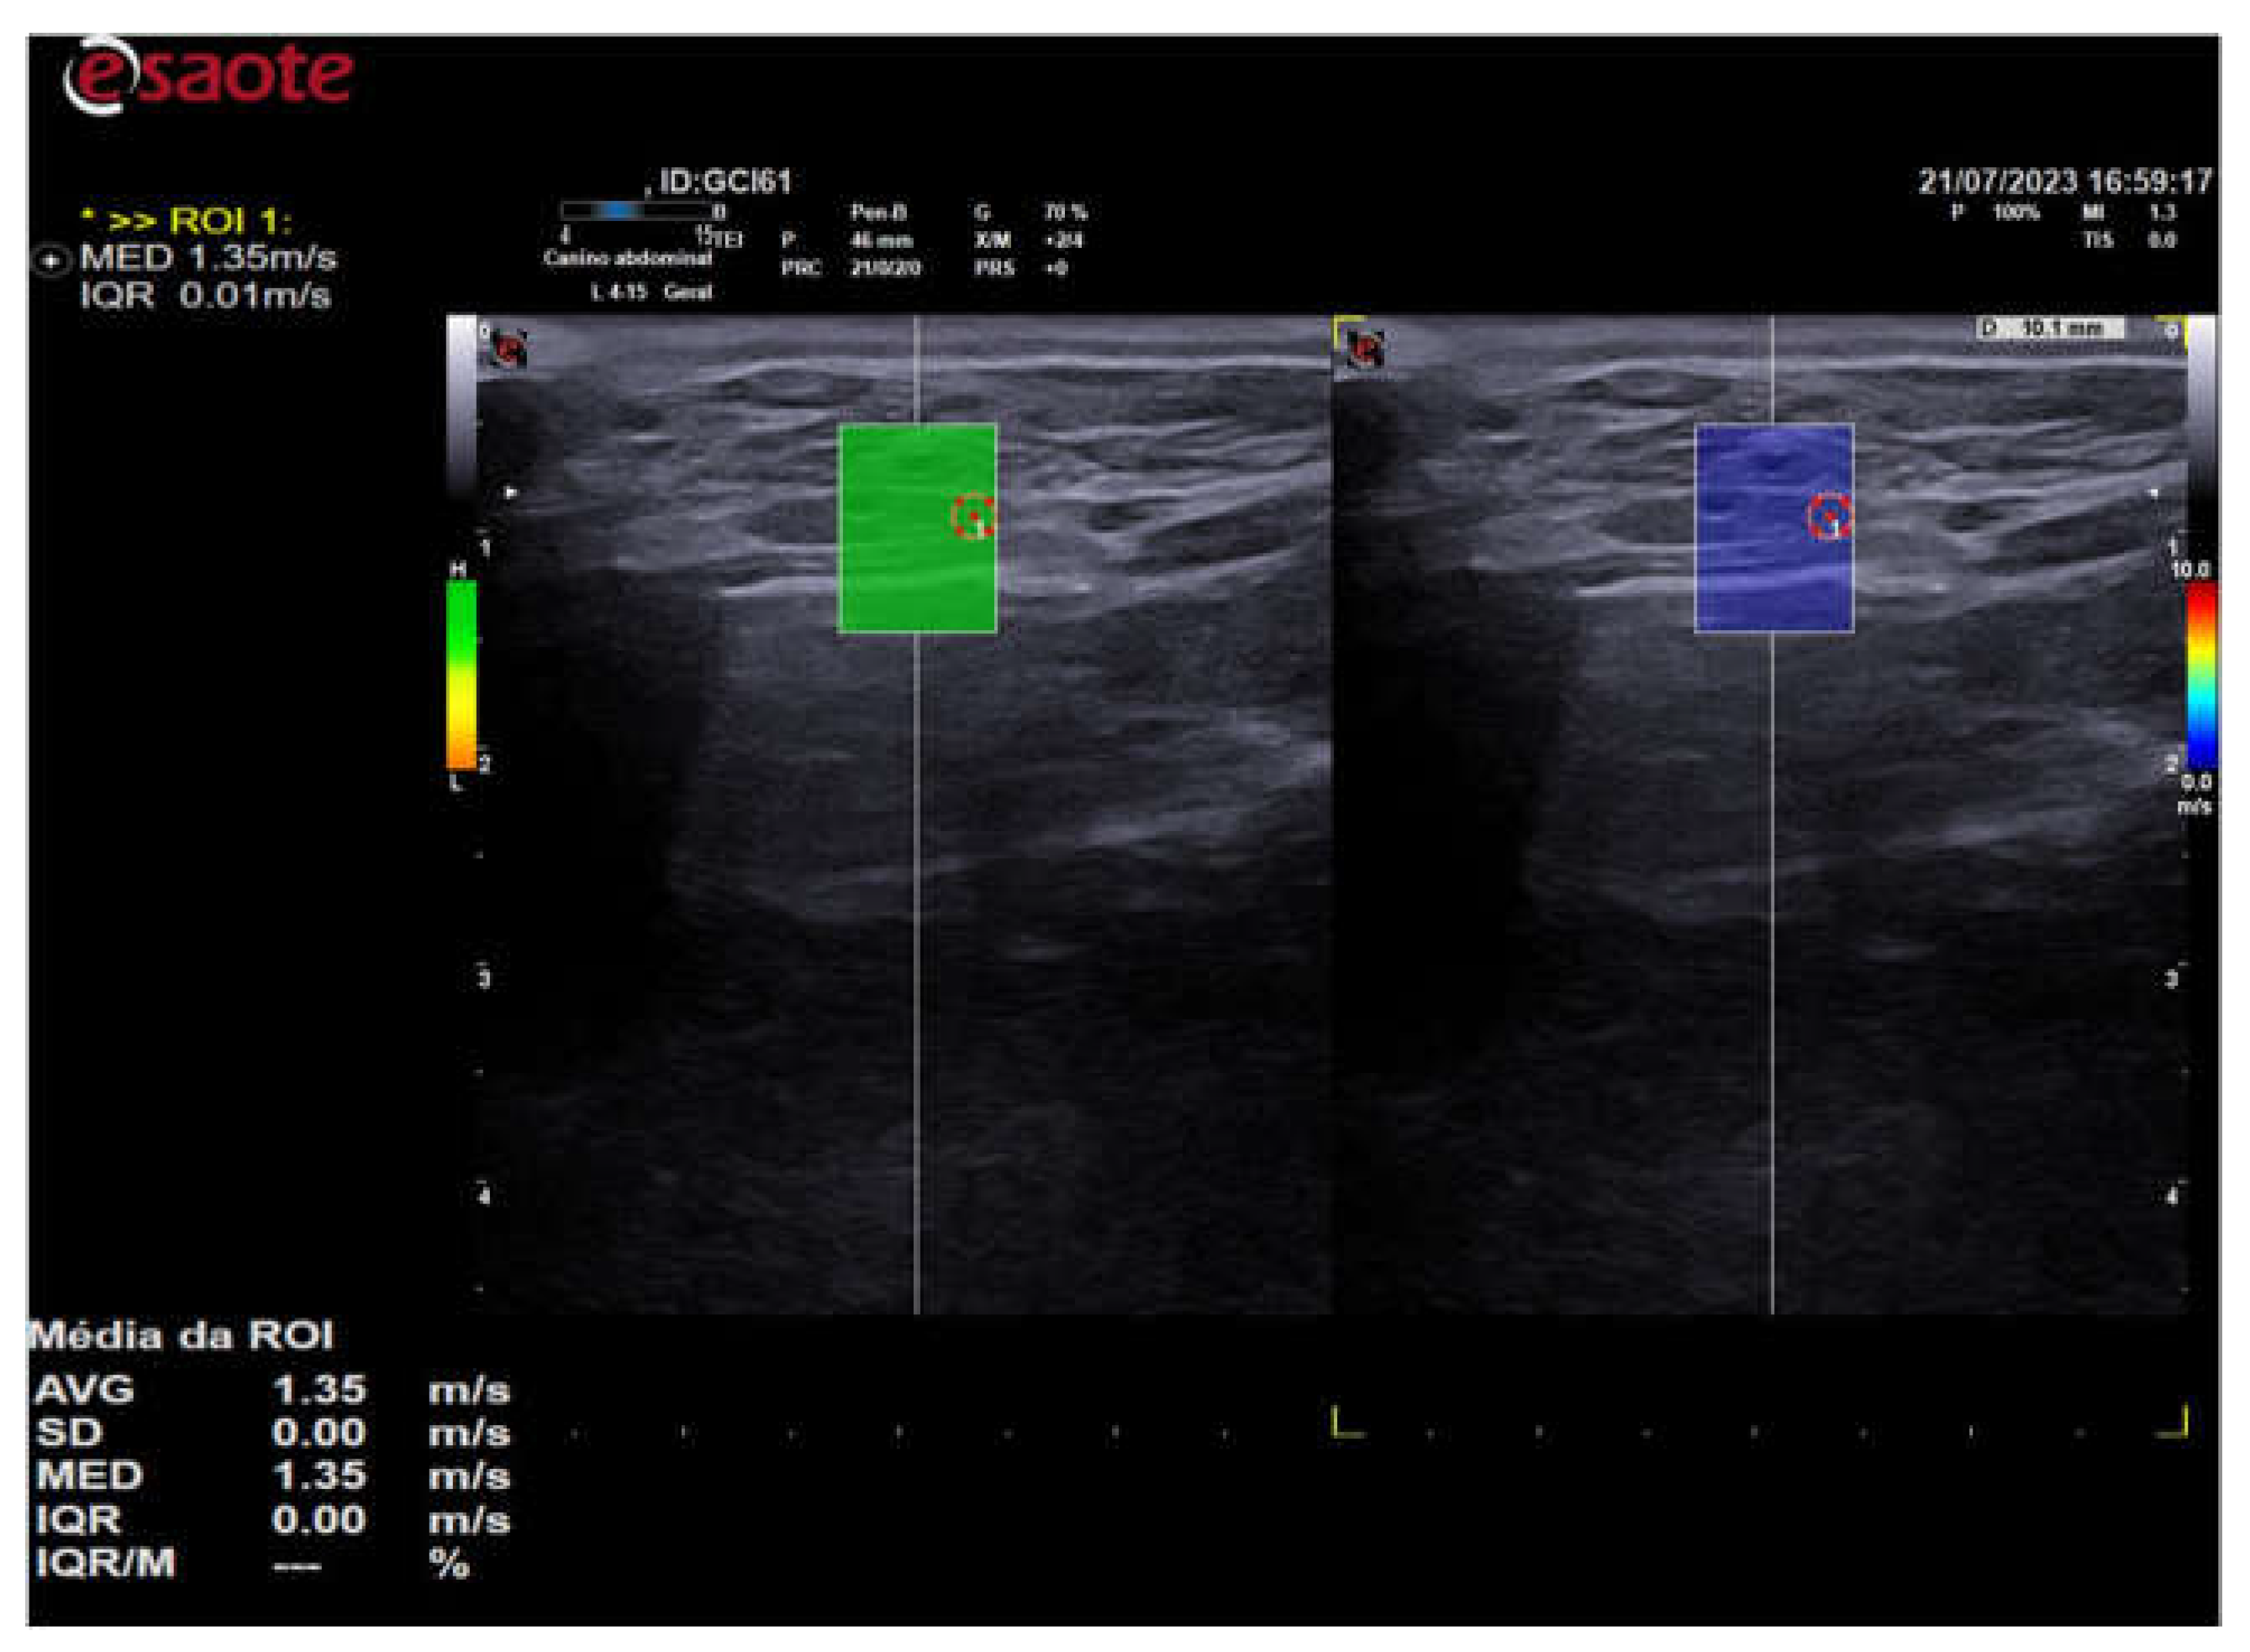

The elastographic images were taken in the longitudinal plane of each thyroid lobe and a scale of 0.0 to 10.0 m/s was used in all cases. The QelaXtoTM 2D software quality map was activated when one of the thyroid lobes was properly framed in the image. The map indicated the most suitable locations for acquiring the shear wave velocity, with the regions colored in green having high quality (Figure 3), yellow indicating medium quality and orange, low quality (Figure 4).

Figure 3. - 2D shear wave elastography image of the left thyroid lobe of a 10-year-old dog. Elastographic image on the left showing the QelaXtoTM 2D software quality map colored in green, indicating high quality for shear wave velocity measurement (quantitative). Right side of the elastographic image showing the colored elastogram (qualitative) from the QelaXtoTM 2D software in blue, indicating that the thyroid parenchyma had low stiffness (soft).